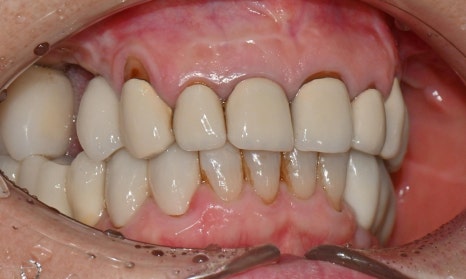

2026.2 치료 마무리 후 사진 - 연세정원치과

이와 같이 임시치아 단계에서 충분히 디자인을 조정하고 상담을 마무리하면, 기공소에 보다 정확한 디자인을 전달할 수 있어 최종 보철 만족도가 크게 높아집니다. 웃을 때나 말할 때 앞니 보철이 보이고, 아래 앞니도 추후 보철 예정이시라서 보철 색상은 다른 보철에 맞추기보다, 환자가 원하는 정도로 밝게 제작하였습니다.